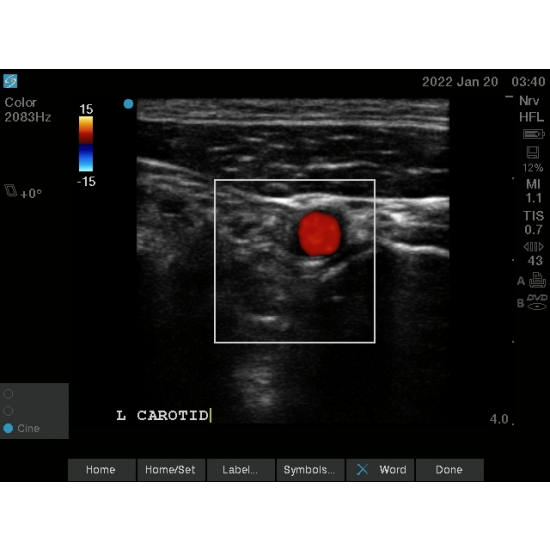

Following a discussion regarding reduction options between conscious sedation versus a regional block, the patient opted for a regional block. An interscalene block was then performed, using a bedside ultrasound. The carotid artery was first identified Case Photo #7 Case Photo #8 . Next, the ultrasound probe was moved posterolaterally until the roots of the brachial plexus were identified Case Photo #3 Case Photo #4 . Under direct ultrasound visualization, 20 milliliters of 2% lidocaine without epinephrine was infiltrated around the nerve roots using a 22 gauge needle Case Photo #5 Case Photo #6 . Concurrently, a nasal cannula with 3 liters oxygen flow was secured onto the patient in anticipation of left diaphragmatic hemiparesis. Ten minutes following the injection, the patient noted subjective shortness of breath but had a normal exam. Shoulder reduction was successful using Matsen's traction-countertraction maneuver with no additional complication.